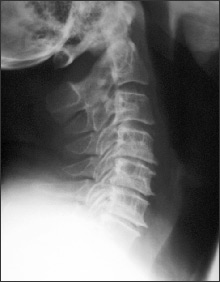

A good start is with x-rays, which allow us to rule out other problems as well. The films also allow us to see if there is any loss of disc space between the vertebrae. If X-Rays indicate serious or advanced disc degeneration, an MRI would be requested.